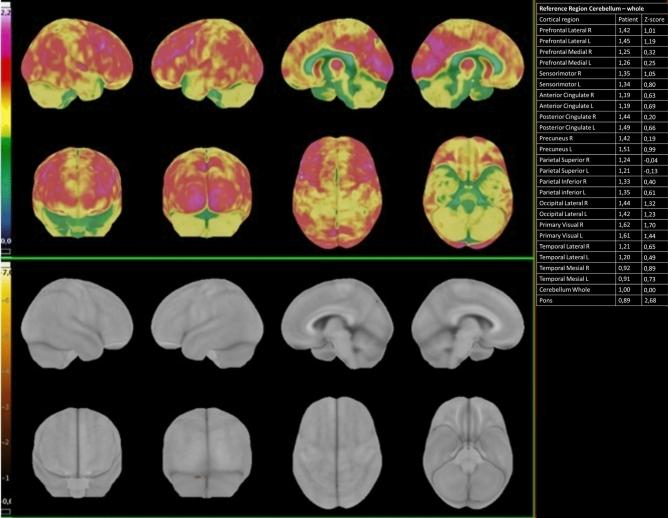

Emerging evidence indicates that the etiologic agent responsible for coronavirus disease 2019 (COVID-19), can cause neurological complications. COVID-19 may induce cognitive impairment through multiple mechanisms. The aim of the present study was to describe the possible neuropsychological and metabolic neuroimaging consequences of COVID-19 12 months after patients' hospital discharge. We retrospectively recruited 7 patients (age [mean ± SD] = 56 years ± 12.39, 4 men) who had been hospitalized for COVID-19 with persistent neuropsychological deficits 12 months after hospital discharge. All patients underwent cognitive assessment and brain (F-FDG) PET/CT, and one also underwent F-amyloid PET/CT. Of the seven patients studied, four had normal glucose metabolism in the brain. Three patients showed various brain hypometabolism patterns: (1) unilateral left temporal mesial area hypometabolism; (2) pontine involvement; and (3) bilateral prefrontal area abnormalities with asymmetric parietal impairment. The patient who showed the most widespread glucose hypometabolism in the brain underwent an F-amyloid PET/CT to assess the presence of Aβ plaques. This examination showed significant Aβ deposition in the superior and middle frontal cortex, and in the posterior cingulate cortex extending mildly in the rostral and caudal anterior cingulate areas. Although some other reports have already suggested that brain hypometabolism may be associated with cognitive impairment at shorter intervals from SarsCov-2 infection, our study is the first to assess cognitive functions, brain metabolic activity and in a patient also amyloid PET one year after COVID-19, demonstrating that cerebral effects of COVID-19 can largely outlast the acute phase of the disease and even be followed by amyloid deposition.

新出现的证据表明,导致 2019 年冠状病毒病(COVID-19)的病原体能够引起神经系统并发症。COVID-19 可能通过多种机制导致认知障碍。本研究旨在描述 COVID-19 患者出院后 12 个月时可能出现的神经心理学和代谢神经影像学后果。我们回顾性招募了 7 名(年龄[均值±标准差] = 56 岁±12.39,4 名男性)因 COVID-19 住院且出院后 12 个月仍存在持续性神经心理学缺陷的患者。所有患者均接受认知评估和脑(F-FDG)PET/CT 检查,其中 1 名患者还接受了 F-淀粉样蛋白 PET/CT 检查。在研究的 7 名患者中,4 名患者的大脑葡萄糖代谢正常。3 名患者表现出不同的脑代谢低下模式:(1)左侧颞内侧区域单侧代谢低下;(2)桥脑受累;(3)额区双侧异常伴顶叶不对称损害。脑葡萄糖代谢最广泛低下的患者接受了 F-淀粉样蛋白 PET/CT 检查,以评估 Aβ斑块的存在。该检查显示在额中回和后扣带回皮质有显著的 Aβ沉积,在前扣带区的头侧和尾侧轻度延伸。尽管其他一些报告已经表明,脑代谢低下可能与 SARS-CoV-2 感染后较短时间的认知障碍有关,但我们的研究首次在 COVID-19 后 1 年评估认知功能、脑代谢活性,并且在 1 名患者中还评估了淀粉样蛋白 PET,表明 COVID-19 的大脑影响可能在疾病的急性期后持续很长时间,甚至可能出现淀粉样蛋白沉积。